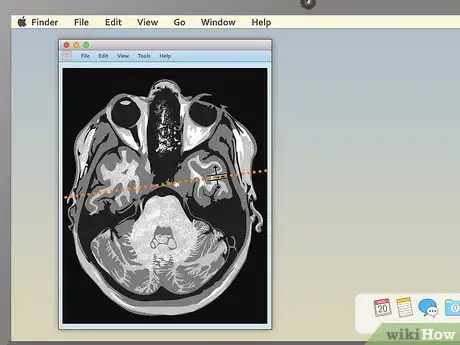

4. 4

Use the section-cut line to see where cross-sections are located. If you display a cross-sectional image along with a sagittal or coronal image, you may see a section-cut line on the second image. This will be a straight line running through the image, but it may not be present on all MRIs. If your image does have one, this shows where on the second image the cross section is located. You should be able to move the section cut line toward the center, right or left of the image. This will change the larger layout image to show the body from the new direction of the scan.

• The section-cut line on the layout picture also shows the direction that the image was taken from. For example, if your MRI were a picture of an everyday object, like a tree, the section cut line might show you if the picture was taken from above in a plane, from a second-story window, or from the ground.